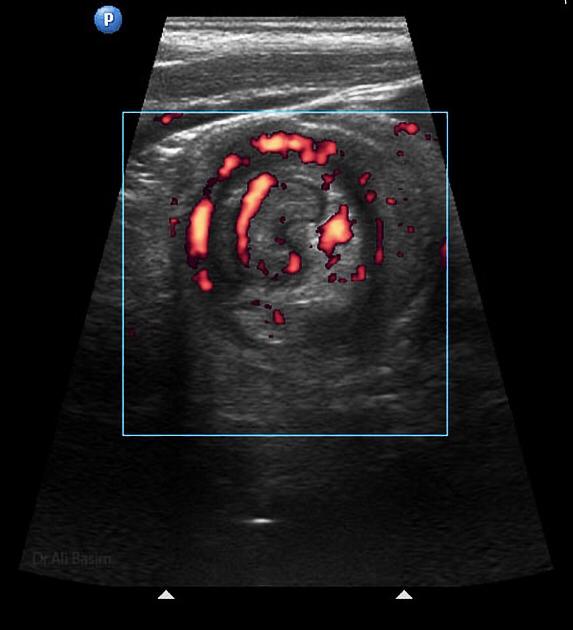

Ultrasonido de Glándula Tiroides

El término nódulo tiroideo se refiere a cualquier crecimiento anormal de las células tiroideas que forman un tumor dentro de la tiroides. Aunque la gran mayoría de los nódulos tiroideos son benignos (no cancerosos), una pequeña proporción de estos nódulos sí...